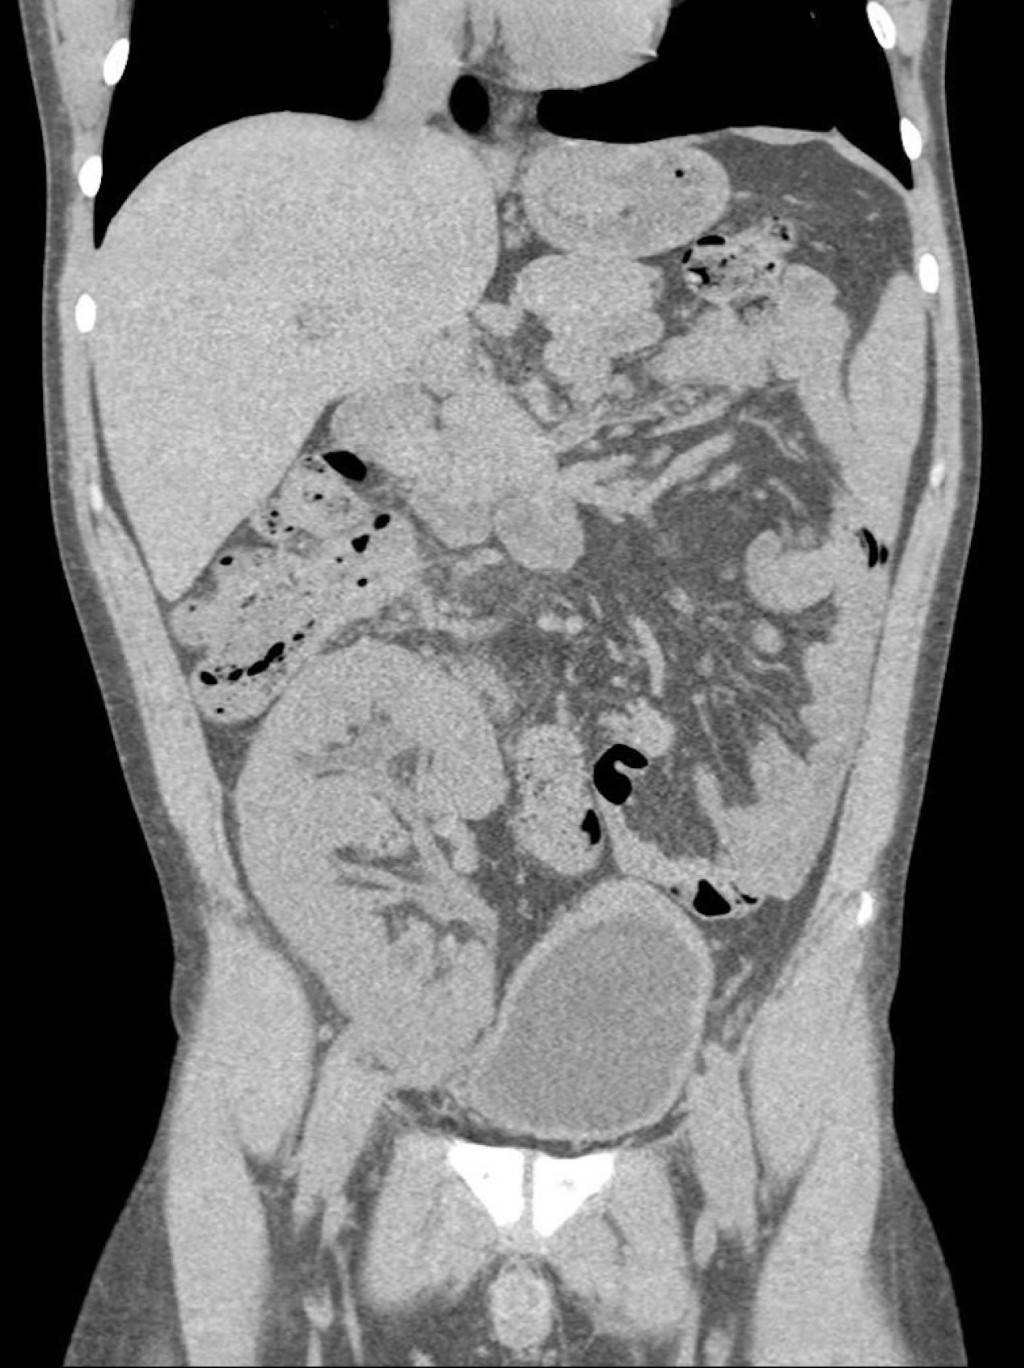

Durante su estancia, presentó orquiepididimitis aguda izquierda, confirmada por ultrasonido Doppler testicular (Figura 1). Se inició terapia con carbapenémico y fluoroquinolona sin éxito. Una tomografía abdominal mostró pielonefritis aguda del injerto renal, clasificada como grado 2 según Huang-Tseng (Figura 2).6 A pesar de la indicación inicial de trasplantectomía, se optó por tratamiento con piperacilina-tazobactam, logrando mejoría clínica y posteriormente el alta.

Figura 2